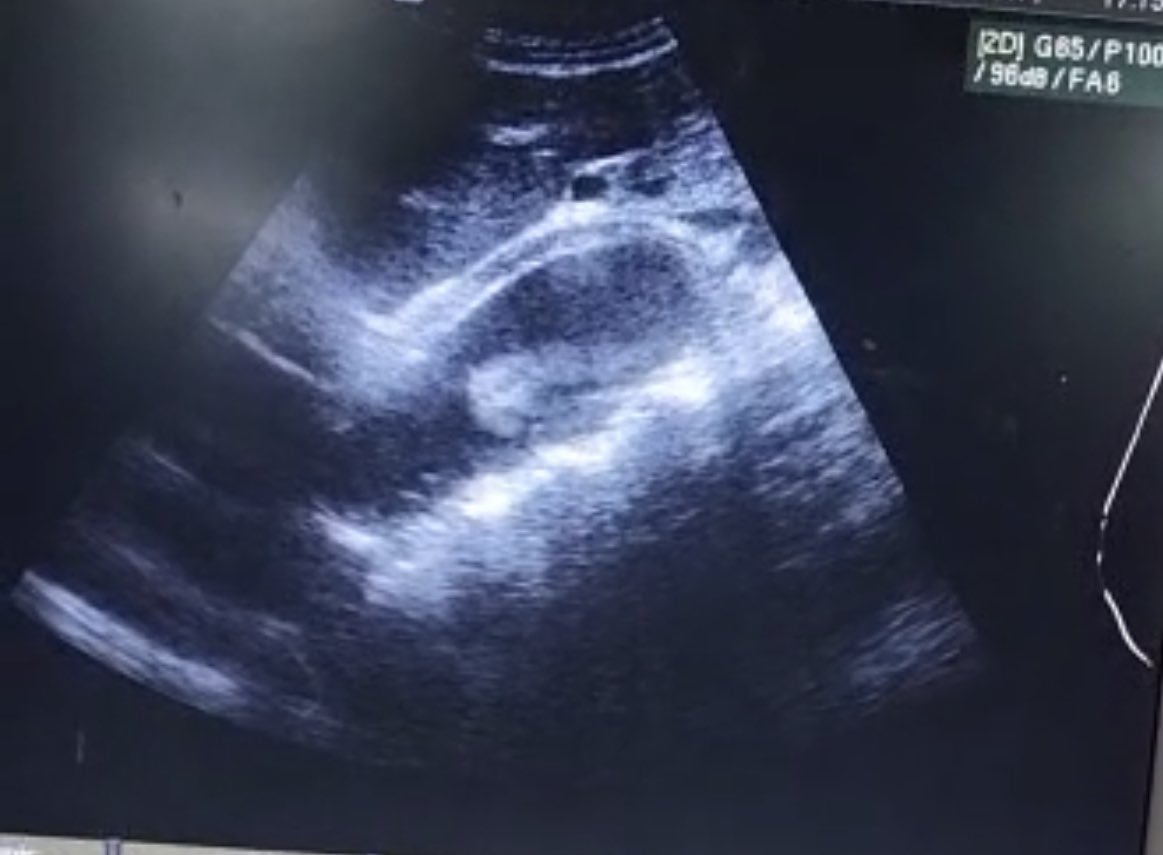

Last 48 hours , 2 of these .50 y/o both came the CP. One typical presentation the other not so typical. #POCUS with ultrasound machine available as part of assessment and 👇🏾. Followed with a CTA which 👍🏾 an aortic dissection #pocusfirst #MedTwitter

adomakoeugene_k's tweet image. Last 48 hours , 2 of these .50 y/o both came the CP.  One typical presentation the other not so typical. #POCUS  with ultrasound machine available as part of assessment and 👇🏾. Followed with a CTA which 👍🏾 an aortic dissection #pocusfirst #MedTwitter